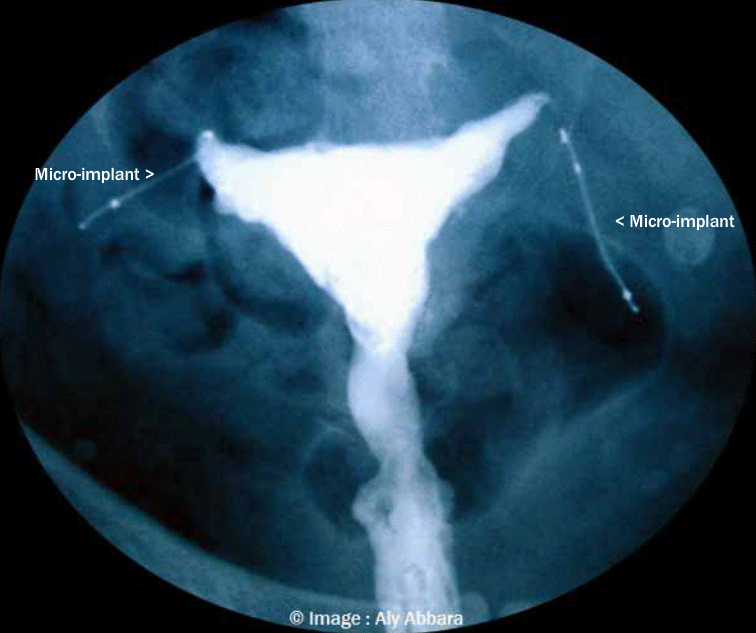

L'aspect hystérographique des deux dispositifs contraceptifs intra-tubaires trois mois après leur insertion dans les trompes avec l'attestation de l'obturation tubaire bilatérale La distance séparant les extrémités proximales des micro-implants est exagérée. |